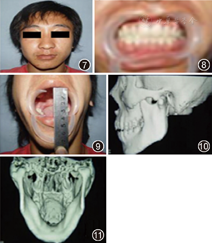

像保守治疗5年后:①面形不对称,颏部略向左偏,咬合关系正常,中线无偏斜,张口度40 mm,开口型无偏斜,下颌前伸和侧向运动正常,颞下颌关节区无疼痛及弹响;②CT可见患侧髁突畸形愈合,髁头分叉缩至髁突上端,外形接近正常髁突,双侧下颌支高度未见明显异常(图7,图8,图9,图10,图11)。

保守治疗7年后:①面形轻度不对称,颏部略向左偏。咬合关系正常,中线无偏斜,张口度40 mm,开口型无偏斜,下颌前伸和侧向运动正常,颞下颌关节区无疼痛及弹响;②CT可见患侧髁突矢状骨折畸形愈合,髁头形态接近正常,患侧关节间隙存在,双侧下颌升支高度未见明显异常(图12,图13,图14,图15,图16)。